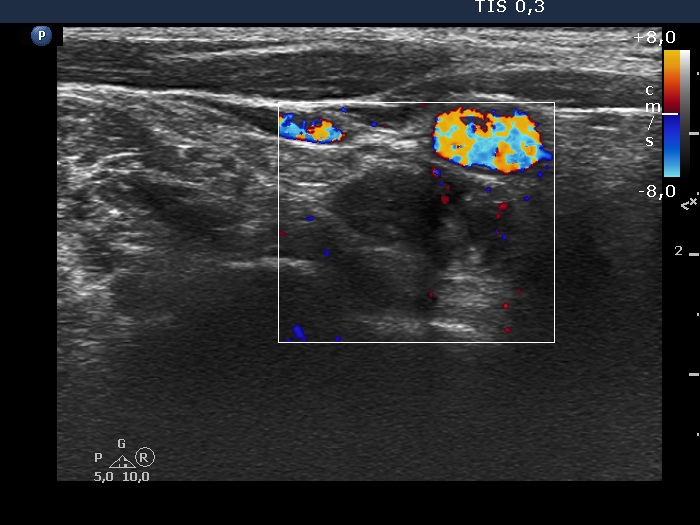

Right lobe, longitudinal scan

Lower part of the right lobe, transverse view, color Doppler mode. The nodule has scanty vascularity.